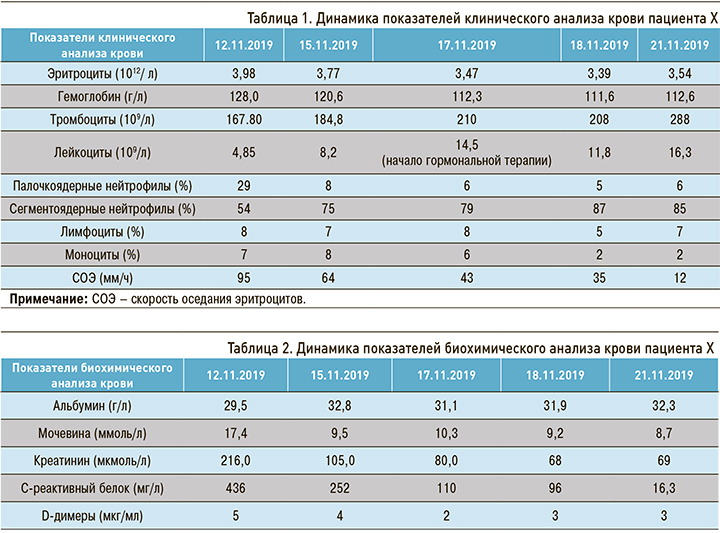

При анализе лабораторных исследований обратила на себя внимание выраженная лимфопения, лейкоцитарный сдвиг влево, увеличение скорости оседания эритроцитов (СОЭ) в 5 раз, увеличение D-димеров в 10 раз (табл. 1). Также мы зафиксировали признаки почечной недостаточности – повышение уровня креатинина более 200 мкмоль/л (табл. 2).

При компьютерной томографии (КТ) органов грудной клетки обнаружена картина двусторонней полисегментарной пневмонии (субтотальная справа). Очаги поражения ткани легкого выглядели как очаги затемнения в виде «матового стекла». В правой плевральной полости присутствовал выпот с компрессией правого легкого, также визуализировались следы выпота в левой плевральной полости. Лимфаденопатия средостения. Легочная гипертензия. Признаков тромбоэмболии легочной артерии (ТЭЛА) по данным КТ органов грудной клетки обнаружено не было, однако отмечалось повышение уровня D-димера (рис. 1).